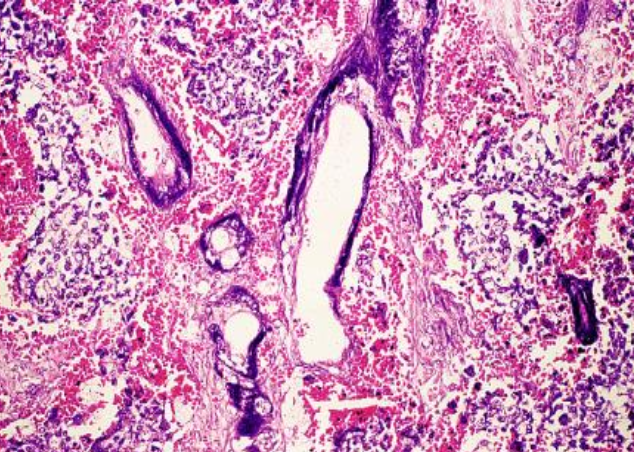

<p>¿Qué es?</p>

Tumor metastasico

Tumores metastásicos características

• Patrón de crecimiento variable

Tumor metastásico